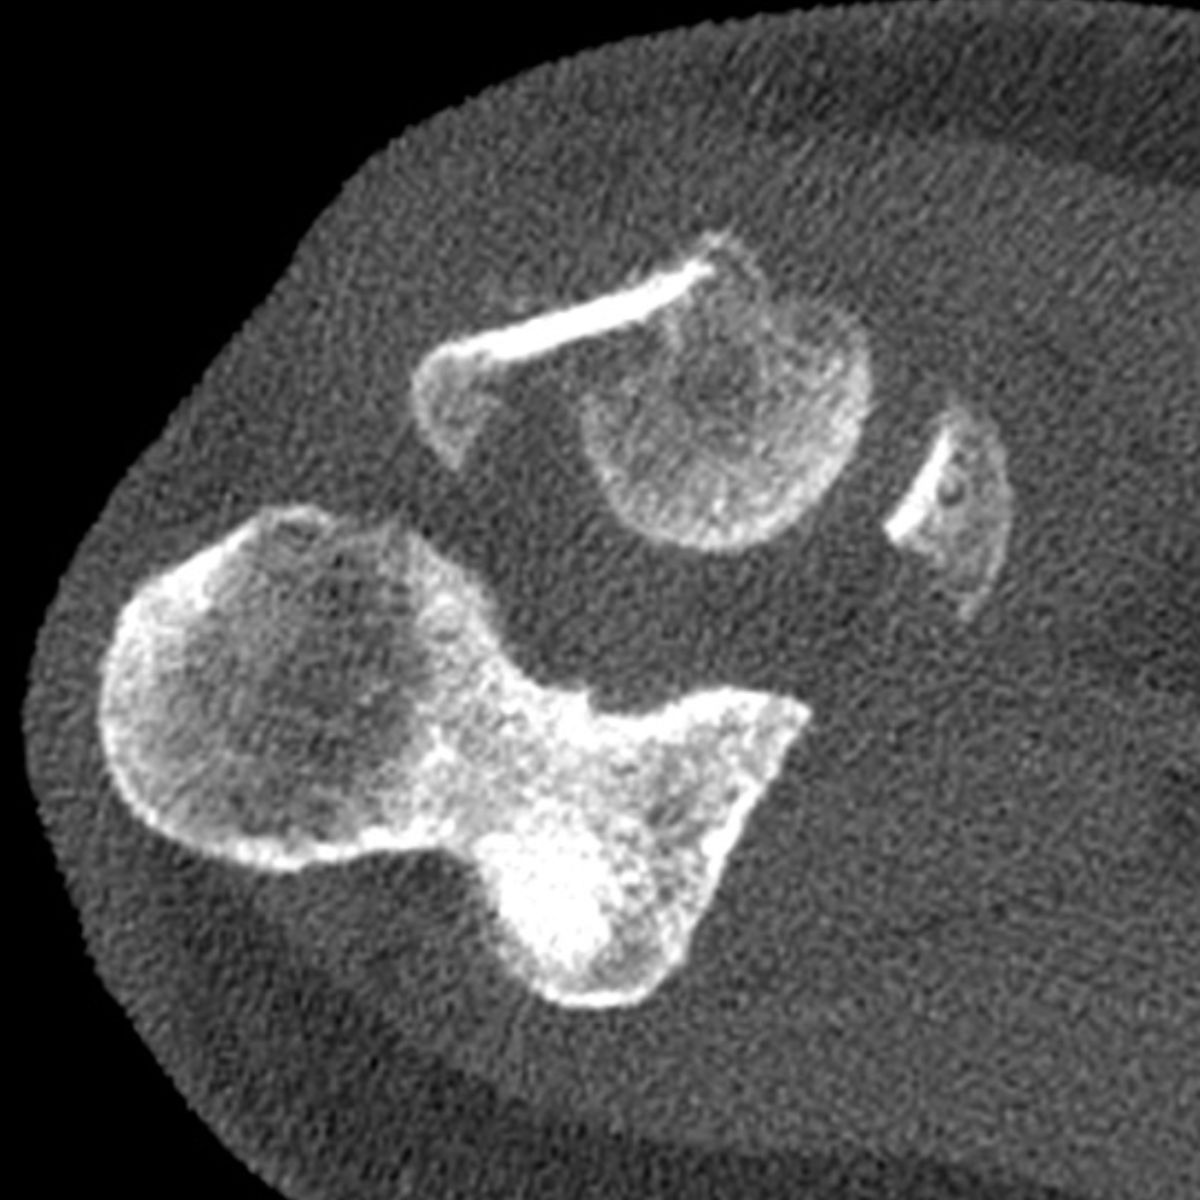

Les radiographies du coude, de face et de profil, suffisent généralement pour faire le diagnostic. En cas de doute, on peut compléter le bilan par un scanner.

En effet, la fracture peut être associée à d’autres fractures du coude, et parfois à des lésions ligamentaires dans le cadre d’une luxation du coude.